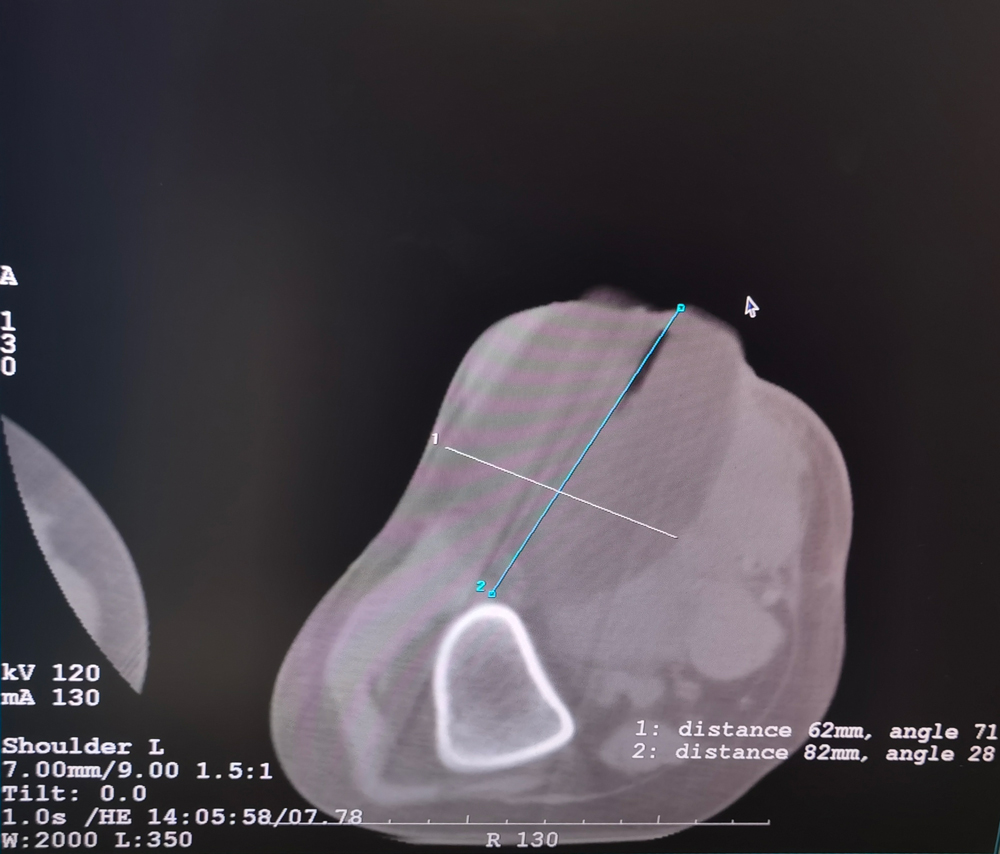

患者二

女,42岁,复发性脂肪瘤,病灶位于右侧膝关节,直径大小13cm。采用双针方案,共进行6个冻融循环,最大冰球直径达8.2cm,术中多方位治疗全面覆盖病灶范围。患者术后状况良好。